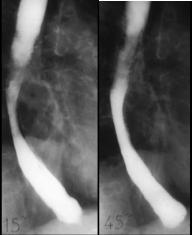

Image radiologique une DES . Les

spasme de owsophage le plus souvent situe au portion

inferieure de oesophage. Bord irregulie et spastique

de oesophage voyait si net le cliche de face |

Image radiologique une DES au

temps d'evacuation de baryte |